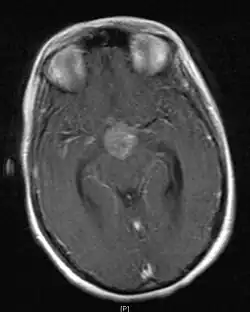

• Mainly located in midline structures, suprasellar region or pineal gland, also basal ganglia and hypothalamus

• Bifocal germinomas (synchronous suprasellar and pineal tumors) regarded as M+ in USA but M0 in Europe

Location